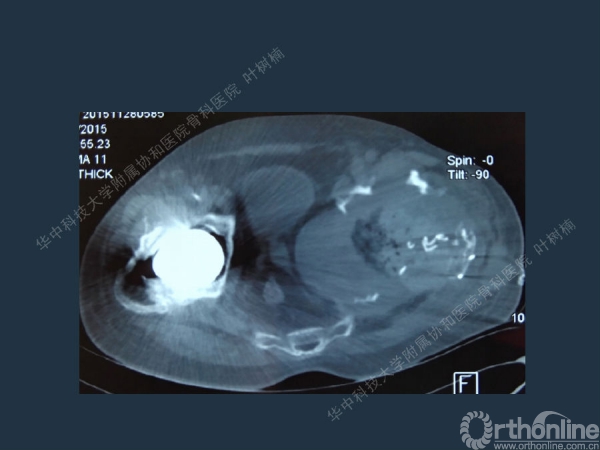

股骨侧翻修

髋臼缺损的处理